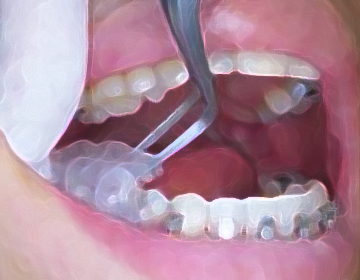

白須賀インダイレクト法で正確に装着します。

噛み合わせを変化させ顎を3次元的に動かします、歯の噛み合わせの上に材料を盛って噛み合わせを変えます。